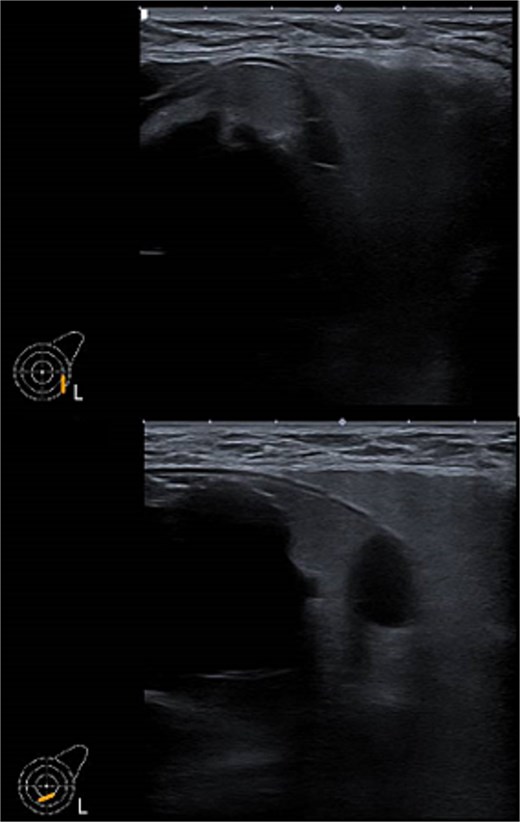

One week later, the patient reported a new lump in the left supraclavicular area. Examination revealed a 2 × 3 cm, nontender, mobile mass, confirmed by ultrasound to be silicone deposition (Figs 3 and 4). Increased breast swelling and lymphadenopathy were attributed to implant rupture and silicone migration.

Typical snowstorm appearance of supraclavicular silicone lymphadenopathy.